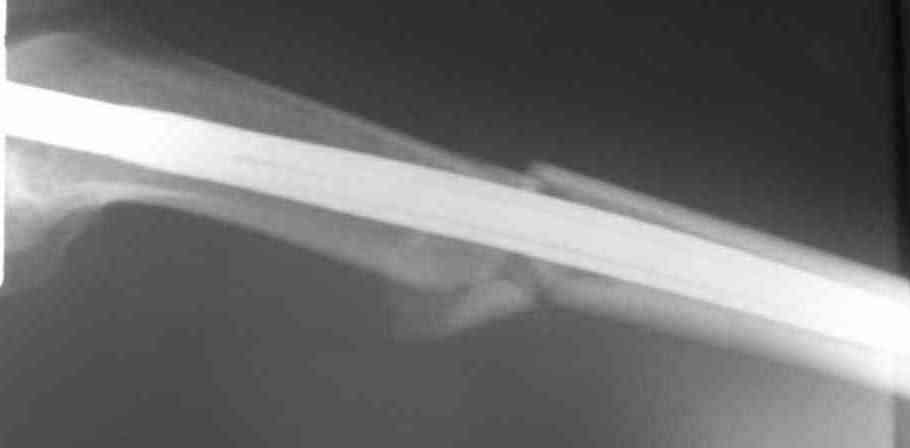

Вчера первый раз синтезировали голень гвоздем Fixion.

Спиральный оскольчатый перелом, ниже середины, у молодого парня. Сделали "классический" вариант гвоздя, который еще без винтов. Получилось все легко. Не торопясь, сделали операцию минут за 20. См. фото.